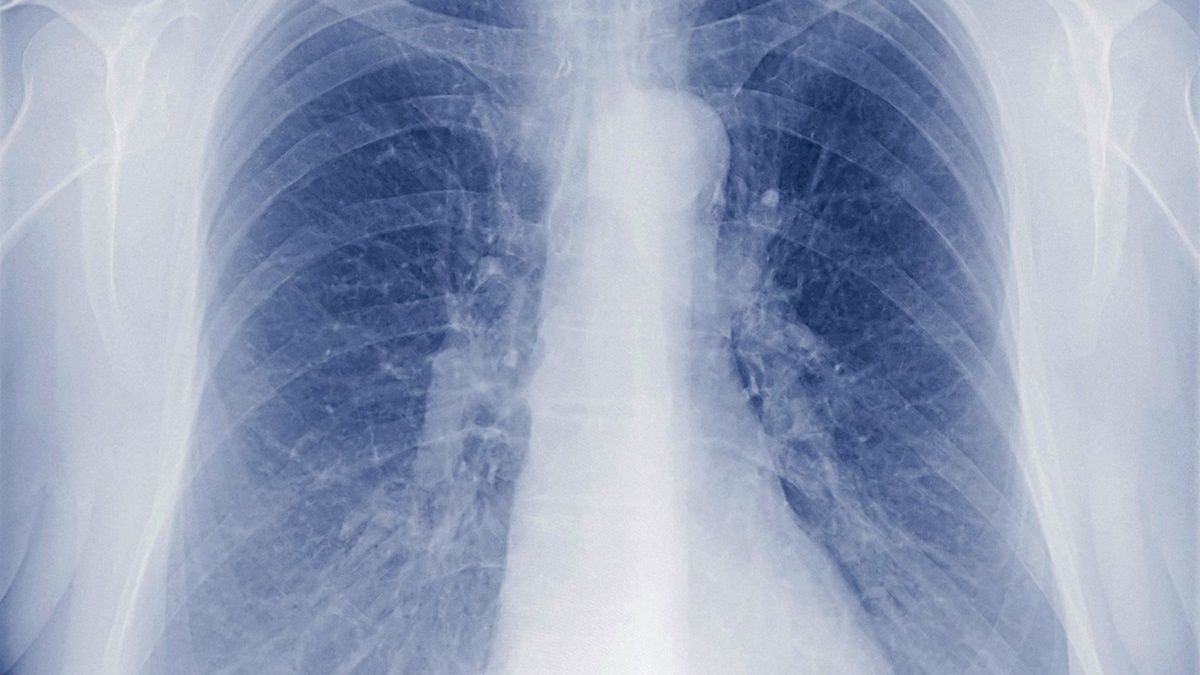

Pluca Po Koronawirusie

Gdy Pluca Chore Koronawirus Grozniejszy Technika I Sprzet Stomatologiczny